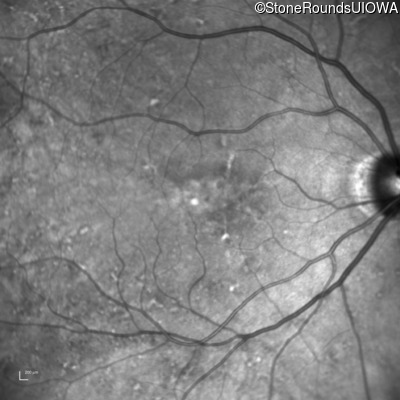

Infrared Fundus Photograph - Right - 20/25

Exemplar